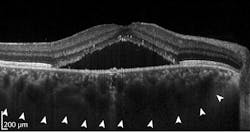

Millions of optical coherence tomography (OCT) images are acquired each year, providing anatomical insights to diagnose numerous medical conditions, including diabetic macular edema (DME). Deep learning is a form of artificial intelligence (AI) in which large amounts of data are processed to combine key factors and predict an output. Deep learning needs an ample database to reach conclusions. OCT generates abundant data, but needs more-efficient data analysis. It’s a natural fit, and an area of burgeoning activity (see figure).

Sina Farsiu, director of the Vision and Image Processing Laboratory at Duke University (Durham, NC), leads a team looking to optimize treatment of diabetic retinopathy (DR). Advanced DR blocks existing retinal blood vessels and triggers formation of new ones. The current standard of care is to treat every patient with antivascular endothelial growth factor (anti-VEGF) drugs, and then see if the patient responds. Many DR patients will not, and that, the team notes, is “costly and burdensome for both patients and physicians.” Farsiu’s goal was to classify responsive and unresponsive patients by analyzing a single pre-treatment OCT image set.

They collected a database of images from 127 patients, all with diabetic macular edema, which is fluid leakage that thickens the retina and degrades vision. All patients were treated with one of the standard anti-VEGF drugs at four- to six-week intervals. After three treatments, OCT images were again acquired, reflecting the clinical practice of evaluating patients’ response at that time. Members of the study group were classified as “responsive” if the retinal thickness decreased by at least 10%, and “nonresponsive” otherwise. Eighty of the patients were responsive and 47 nonresponsive, consistent with percentages in the general population.

Farsiu’s team created a CNN architecture with six “attention blocks,” which are essentially elements that allow the network to weight “interesting” image areas more heavily. They compared the CNN performance against that of several popular learning architectures. Their architecture significantly outperformed the alternatives, with 87% precision and 85% specificity. Performance for very responsive and very unresponsive patients was even better. The team concluded that “the ability to accurately select highly responsive and very poorly responsive patients prior to treatment would be beneficial for practicing physicians and potentially for subject selection in clinical trials of novel therapies for DME.”